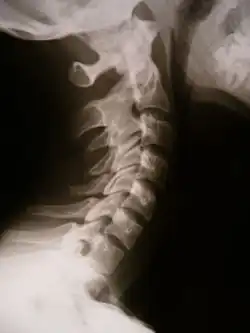

X-ray showing synostosis in the cervical spine

Synostosis (plural: synostoses) is fusion of two or more bones. It can be normal in puberty, fusion of the epiphyseal plate to become the epiphyseal line, or abnormal. When synostosis is abnormal it is a type of dysostosis. Examples of synostoses include: